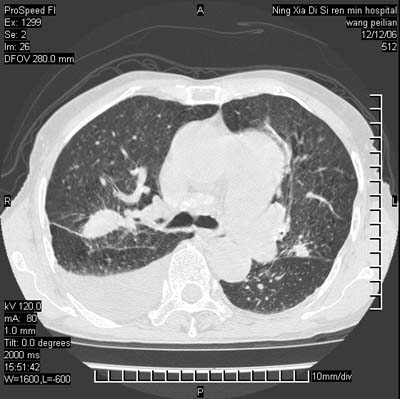

两肺可见多个大小不等的结节,左侧有胸水,纵隔淋巴结增大,考虑是细支气管肺泡癌

两肺尖纤维索状影,两下肺结节块状影,且有钙化灶,右胸腔积液。考虑肺结核并胸膜炎。

双侧肺结核伴右侧胸腔积液.

两肺尖纤维索状影,两下肺结节块状影,且有钙化灶,右胸腔积液。考虑肺结核并胸膜炎肺间质纤维化

两肺以间质性病变为主,并有胸腔积液,考虑结核

考虑:1、慢性支气管炎合并全小叶型肺气肿、间质纤维化;

2、双肺结核;

3、右侧胸膜炎(积液)。

1、双肺继发型肺结核(以纤维、增殖灶为主);

2、右侧胸腔积液;

3、其余符合老年肺改变。

双肺见多个结节状及条索状影,双侧胸腔积液,右侧叶间积液,考虑结核性胸膜炎